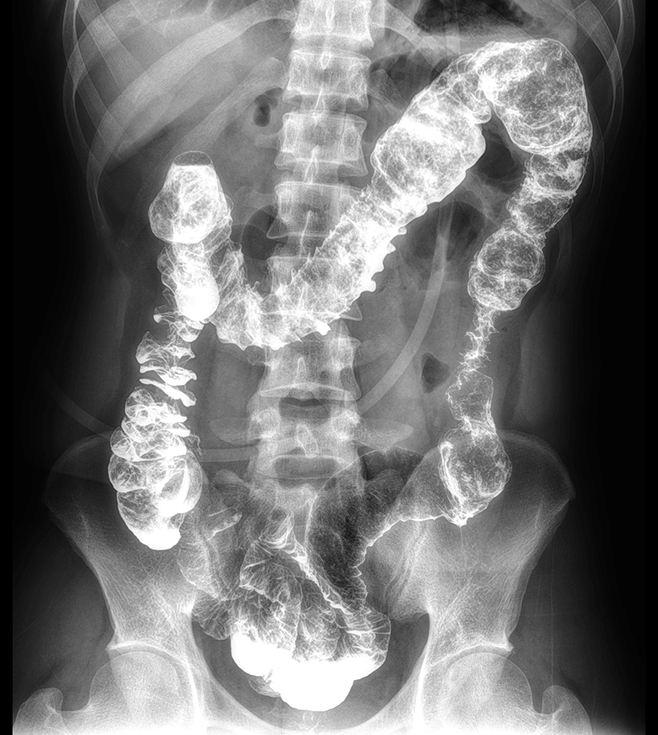

多功能诊断专用动态DR

太阳成集团tyc122cc入口科技全新设计的第四代床式动态DR,集拍片、透视、造影、全身拼接、尘肺体检于一体,一机多能,真正意义上实现全科室应用,提升医院实际效益。

多功能诊断应用专业设计

从医疗机构放射科的实际应用出发,针对多功能诊断进行多维度专业设计,优化病人检查体验,大幅提升操作技师工作效率。

高清动态平板探测器

搭载自主研发超清大视野动态平板探测器,600微米碘化铯大幅提升X线转化效率,独特的非晶硅阵列与高速读取集成电路紧密协作,轻松实现多帧率透视与高清点片。

专业的影像处理系统

“腾灵”系列搭载的IEAE影像处理系统,具备多项发明专利。本系统采用多频域图像处理技术,其6大核心处理模块使影像具有优秀的一致性、柔和性、空间层次感和纹理细腻度,为用户精准诊断病灶奠定了坚实的基础。